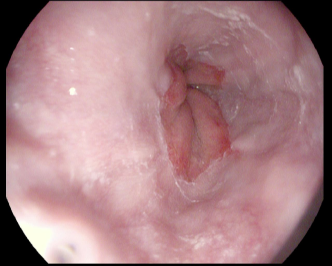

4.1.7 Gastrointestinal endoscopy

Endoscopies are used to detect diseases in the human digestive system. Images from inside the gastrointestinal tract can be used to help doctors detect diseases early. The used dataset 777https://www.kaggle.com/datasets/abdallahwagih/kvasir-dataset-for-classification-and-segmentation contains eight image categories of the digestive system obtained through the endoscopy imaging technique, as shown in Fig. 8. There are a total of 6000600060006000 images that can be used in training and testing machine learning algorithms.

Refer to caption

(a) Normal cecum

(b) Normal pylorus

(c) Normal z-line

(d) Dyed lifted polyps

(e) Dyed resection margins

(f) Esophagitis

(g) Polyps

(h) Ulcerative-colitis

Figure 8: Gastrointestinal endoscopy images.